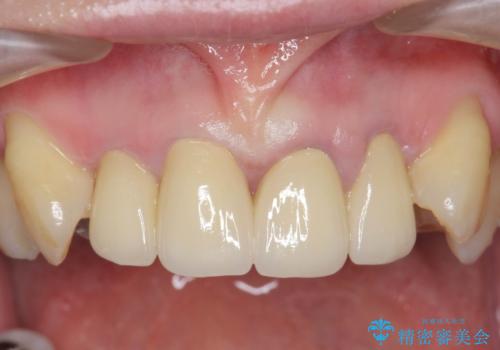

前歯の見た目をオールセラミッククラウンで改善

- 前歯のぐらつき、見た目の改善を希望され来院されました。

ぐらつきのある歯は、破折が認められ、その他前歯も不十分な根管治療や不適合なクラウン、レジン修復により審美障害が起きています。

問題を一つづつ丁寧に解決し、前歯の審美性の改善を計画します。

オールセラミックによる審美的な仕上がりに満足いただくことができました。